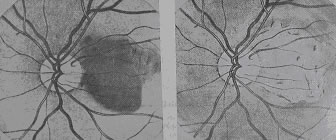

img Choroidal melanoma